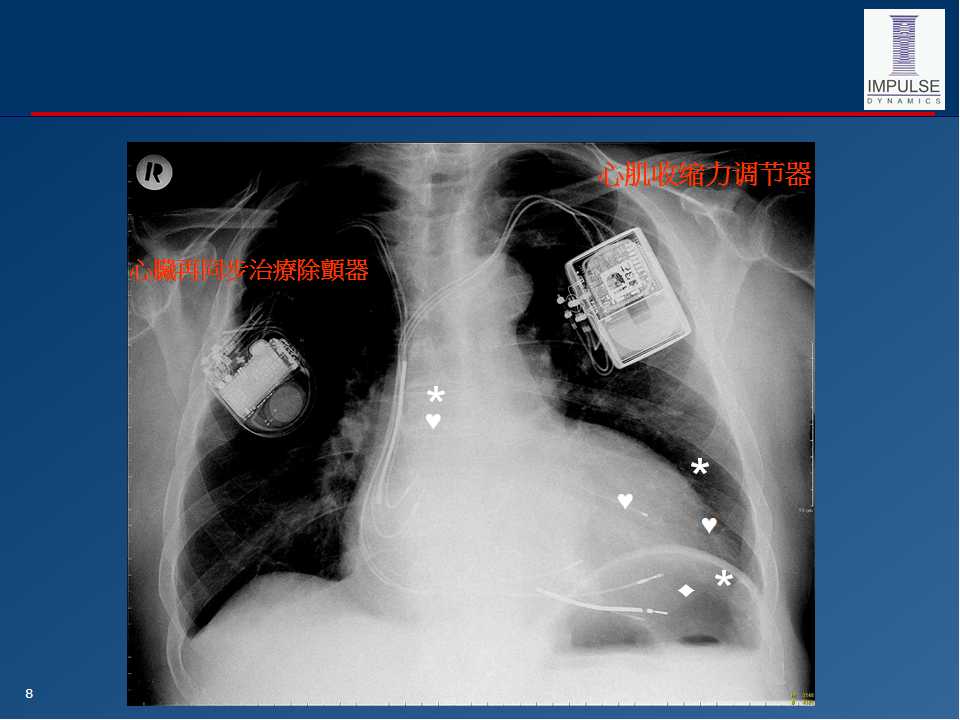

心肌收缩力调节器 (CCM) ------治疗慢性心力衰竭的10年历程